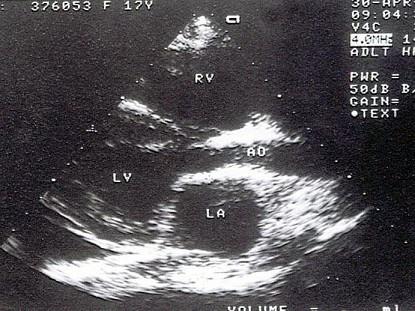

问题 该病例最可能的诊断?(?)

选项 A.高血压病 B.主动脉瓣上缩窄 C.主动脉瓣上膜性狭窄 D.瓣上环形狭窄 E.肥厚性心肌病

答案 B